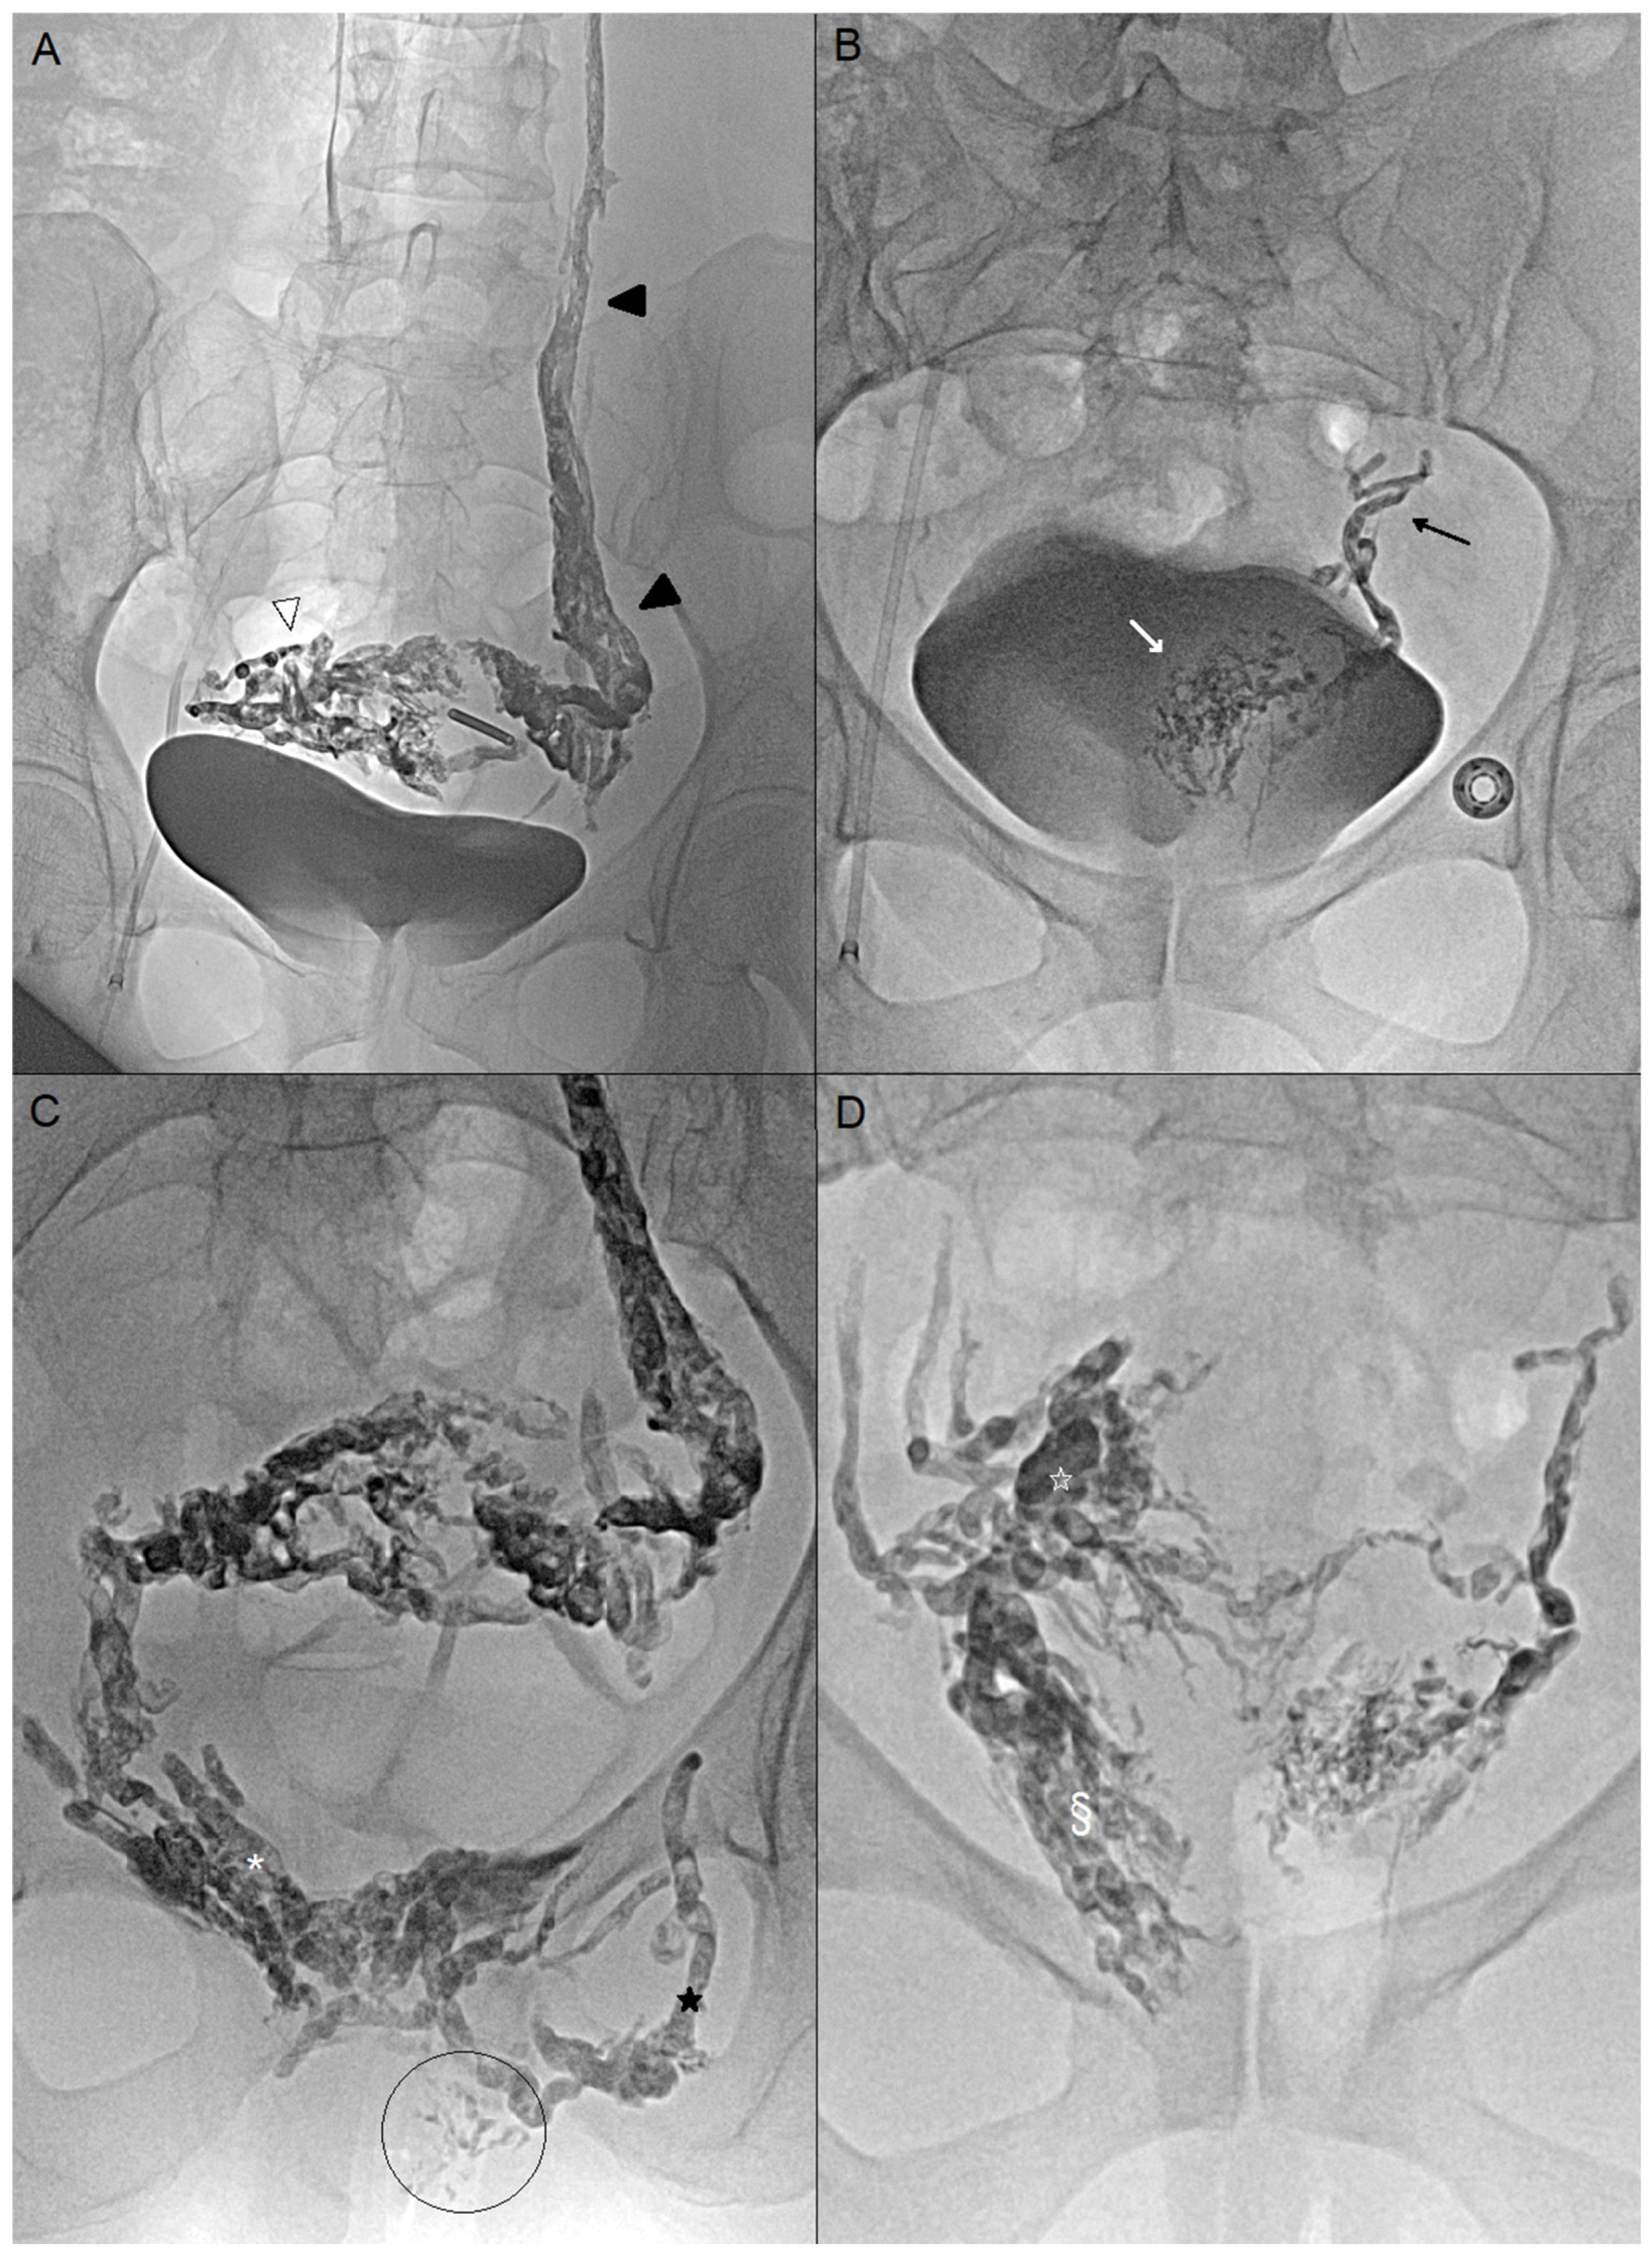

Then, embolization was performed with a liquid agent. Glue was preferred when certain varicose veins were superficial to avoid permanent tattoos [9,10]. Glubran®2 (GEM, Viareggio, Italy) was mixed with Lipiodol® (Guerbet, Paris, France) (ratio 1:1 or 1:2) and injected with 3 mL syringe. At the end of the injection, the needle and superficial varices were flushed with glucose, followed by a 1 min compression of the vulvar puncture site. Ethylene vinyl alcohol copolymer (Onyx®) (Medtronic, Dublin, Ireland) was prepared by agitation for at least 20 min. The needle was rinsed and the dead space was plugged with dimethyl sulfoxide (DMSO). Then, Onyx® was delivered with 1 mL syringe provided. Onyx® was slowly injected under fluoroscopic control (Figure 2).

Figure 2. (A) Endovascular embolization by femoral access of a 45-year-old woman (case n°4). Embolization of the left ovarian vein (black arrowheads) with Onyx, which also enables occlusion of the right peri-uterine varicose veins (white arrowhead) (B) Endovascular embolization of a 35-year-old woman (case n°6). No pathological reflux in the left ovarian vein. Embolization of the left uterine vein (black arrow) and left pericervical varices (white arrow) with Onyx, catheterized using a UAC catheter (Merit Medical, South Jordan, UT, USA) and a Progreat 2.7Fr microcatheter (Terumo, Tokyo, Japan). (C) Case n°4: Percutaneous embolization under endovaginal guidance of the bilateral pudendal veins (white asterisk), the left obturator vein (black star), and vulvar varices (circled area). Glue was preferred due to the presence of superficial vulvar varices. (D) Case n°6: Percutaneous embolization of right perivaginal (§) and periuterine varices (white star) under endovaginal guidance. Onyx was preferred for its slow and controlled progression.